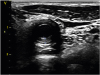

An 18-year-old man was admitted to our department because of arm claudication and right carotidynia. Physical examination revealed loud bruits over the carotid arteries bilaterally and asymmetrical upper limb blood pressure and pulses. Laboratory data showed microscopic anemia along with elevated ESR and CRP at 64 mm/h and 192 mg/L, respectively. Doppler ultrasonography of the neck revealed a long homogeneous, midechoic, circumferential wall thickening of both common carotid arteries (Figures 1 and 2). The Intima-media thickness of the right common carotid artery was 0.17 to 0.26 cm (the maximal normal value is 0.06 cm). This elementary ultrasound lesion, known as “macaroni sign”, is almost pathognomonic of Takayasu arteritis (TA).1) Computed tomography angiography of the aorta and its major branches showed a circumferential mural thickening of the thoracic and abdominal aorta. Furthermore, we noted high-grade stenosis of the following vessels: left subclavian artery, both renal arteries, and both superior and inferior mesenteric arteries.

Although angiography is the gold standard in the diagnosis of TA, it usually misses arterial wall changes particularly in early stage of the disease. On the other hand, ultrasonography is a non-invasive and valuable tool for the diagnosis of early TA; it delineates artery wall swelling which is circumferential, long, and homogeneous. Moreover, ultrasonography is also used to monitor disease activity during the follow-up of patients with TA.